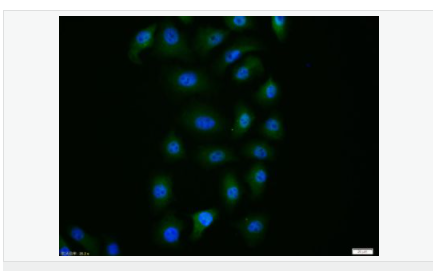

| 產(chǎn)品應(yīng)用 | WB=1:500-2000 ELISA=1:5000-10000 IHC-P=1:100-500 IHC-F=1:100-500 Flow-Cyt=1ug/Test ICC=1:100 IF=1:100-500 (石蠟切片需做抗原修復(fù)) not yet tested in other applications. optimal dilutions/concentrations should be determined by the end user. |

| 產(chǎn)品介紹 | Caspase 9 (also known as ICE like apoptotic protease 6 (ICE LAP6), apoptotic protease Mch6, and apoptotic protease activating factor 3 (Apaf3)) is a member of the peptidase family C14 that contains a CARD domain. This caspase is active as a heterotetramer and has been reported to have two isoforms. ProCaspase 9 has been reported to be approximately 47 kD. This caspase is present in the cytosol and, upon activation, translocates to the mitochondria. Caspase 9 is involved in the caspase activation cascade responsible for apoptosis execution and cleaves/activates Caspase 3 and Caspase 6. Caspase 9 is inhibited by the dominant negative isoform, BclXL, cIAP1, cIAP2, XIAP, and Livin. This caspase becomes activated when recruited to Apaf1/cytochrome c complex, and following cleavage by Apaf1, granzyme B, Caspase 3, possibly Caspase 8 and Caspase 10 into large p37 and small p10 subunits. Caspase 9 intereacts with BIRC7 and has been shown to cleave PARP and vimentin. Function: Involved in the activation cascade of caspases responsible for apoptosis execution. Binding of caspase-9 to Apaf-1 leads to activation of the protease which then cleaves and activates caspase-3. Proteolytically cleaves poly(ADP-ribose) polymerase (PARP). Isoform 2 lacks activity is an dominant-negative inhibitor of caspase-9. Subunit: Heterotetramer that consists of two anti-parallel arranged heterodimers, each one formed by a 35 kDa (p35) and a 10 kDa (p10) subunit. Caspase-9 and APAF1 bind to each other via their respective NH2-terminal CED-3 homologous domains in the presence of cytochrome C and ATP. Interacts (inactive form) with EFHD2. Interacts with HAX1. Interacts with BIRC2/c-IAP1, XIAP/BIRC4, BIRC5/survivin, BIRC6/bruce and BIRC7/livin. Tissue Specificity: Ubiquitous, with highest expression in the heart, moderate expression in liver, skeletal muscle, and pancreas. Low levels in all other tissues. Within the heart, specifically expressed in myocytes. Post-translational modifications: Cleavages at Asp-315 by granzyme B and at Asp-330 by caspase-3 generate the two active subunits. Caspase-8 and -10 can also be involved in these processing events. Phosphorylated at Thr-125 by MAPK1/ERK2. Phosphorylation at Thr-125 is sufficient to block caspase-9 processing and subsequent caspase-3 activation. Similarity: Belongs to the peptidase C14A family. Contains 1 CARD domain. SWISS: P55211 Gene ID: 842 Database links: Entrez Gene: 842 Human Entrez Gene: 12371 Mouse Omim: 602234 Human SwissProt: P55211 Human SwissProt: Q4FJK5 Mouse Unigene: 329502 Human Unigene: 88829 Mouse Unigene: 32199 Rat Important Note: This product as supplied is intended for research use only, not for use in human, therapeutic or diagnostic applications. Caspase-9半胱氨酸蛋白酶家族成員之一,又稱ICE-Lap6(ICE Like apoptotease 6)參與細胞凋亡過程和細胞因子的加工過程,在許多胚胎和成人組織中都有分布。此抗體主要用于腫瘤研究。 |